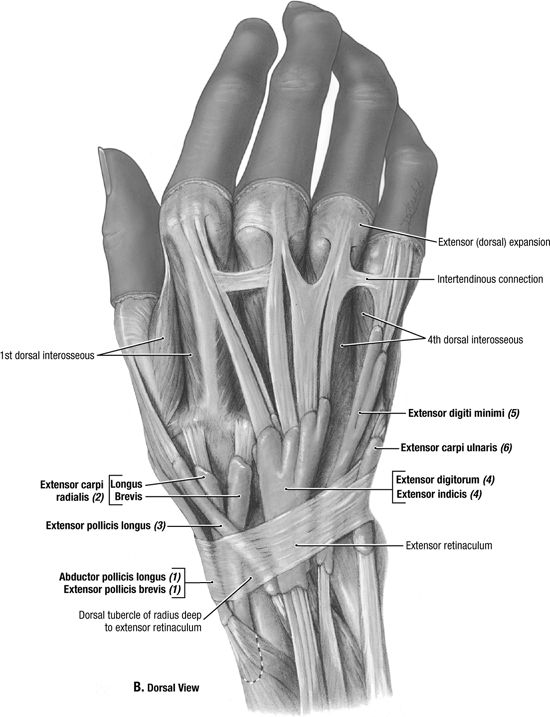

Posterior Subtalar Joint

The Broden view is a useful adjunct view to look at the

posterior subtalar joint to assess for intraarticular fractures and

arthritis.